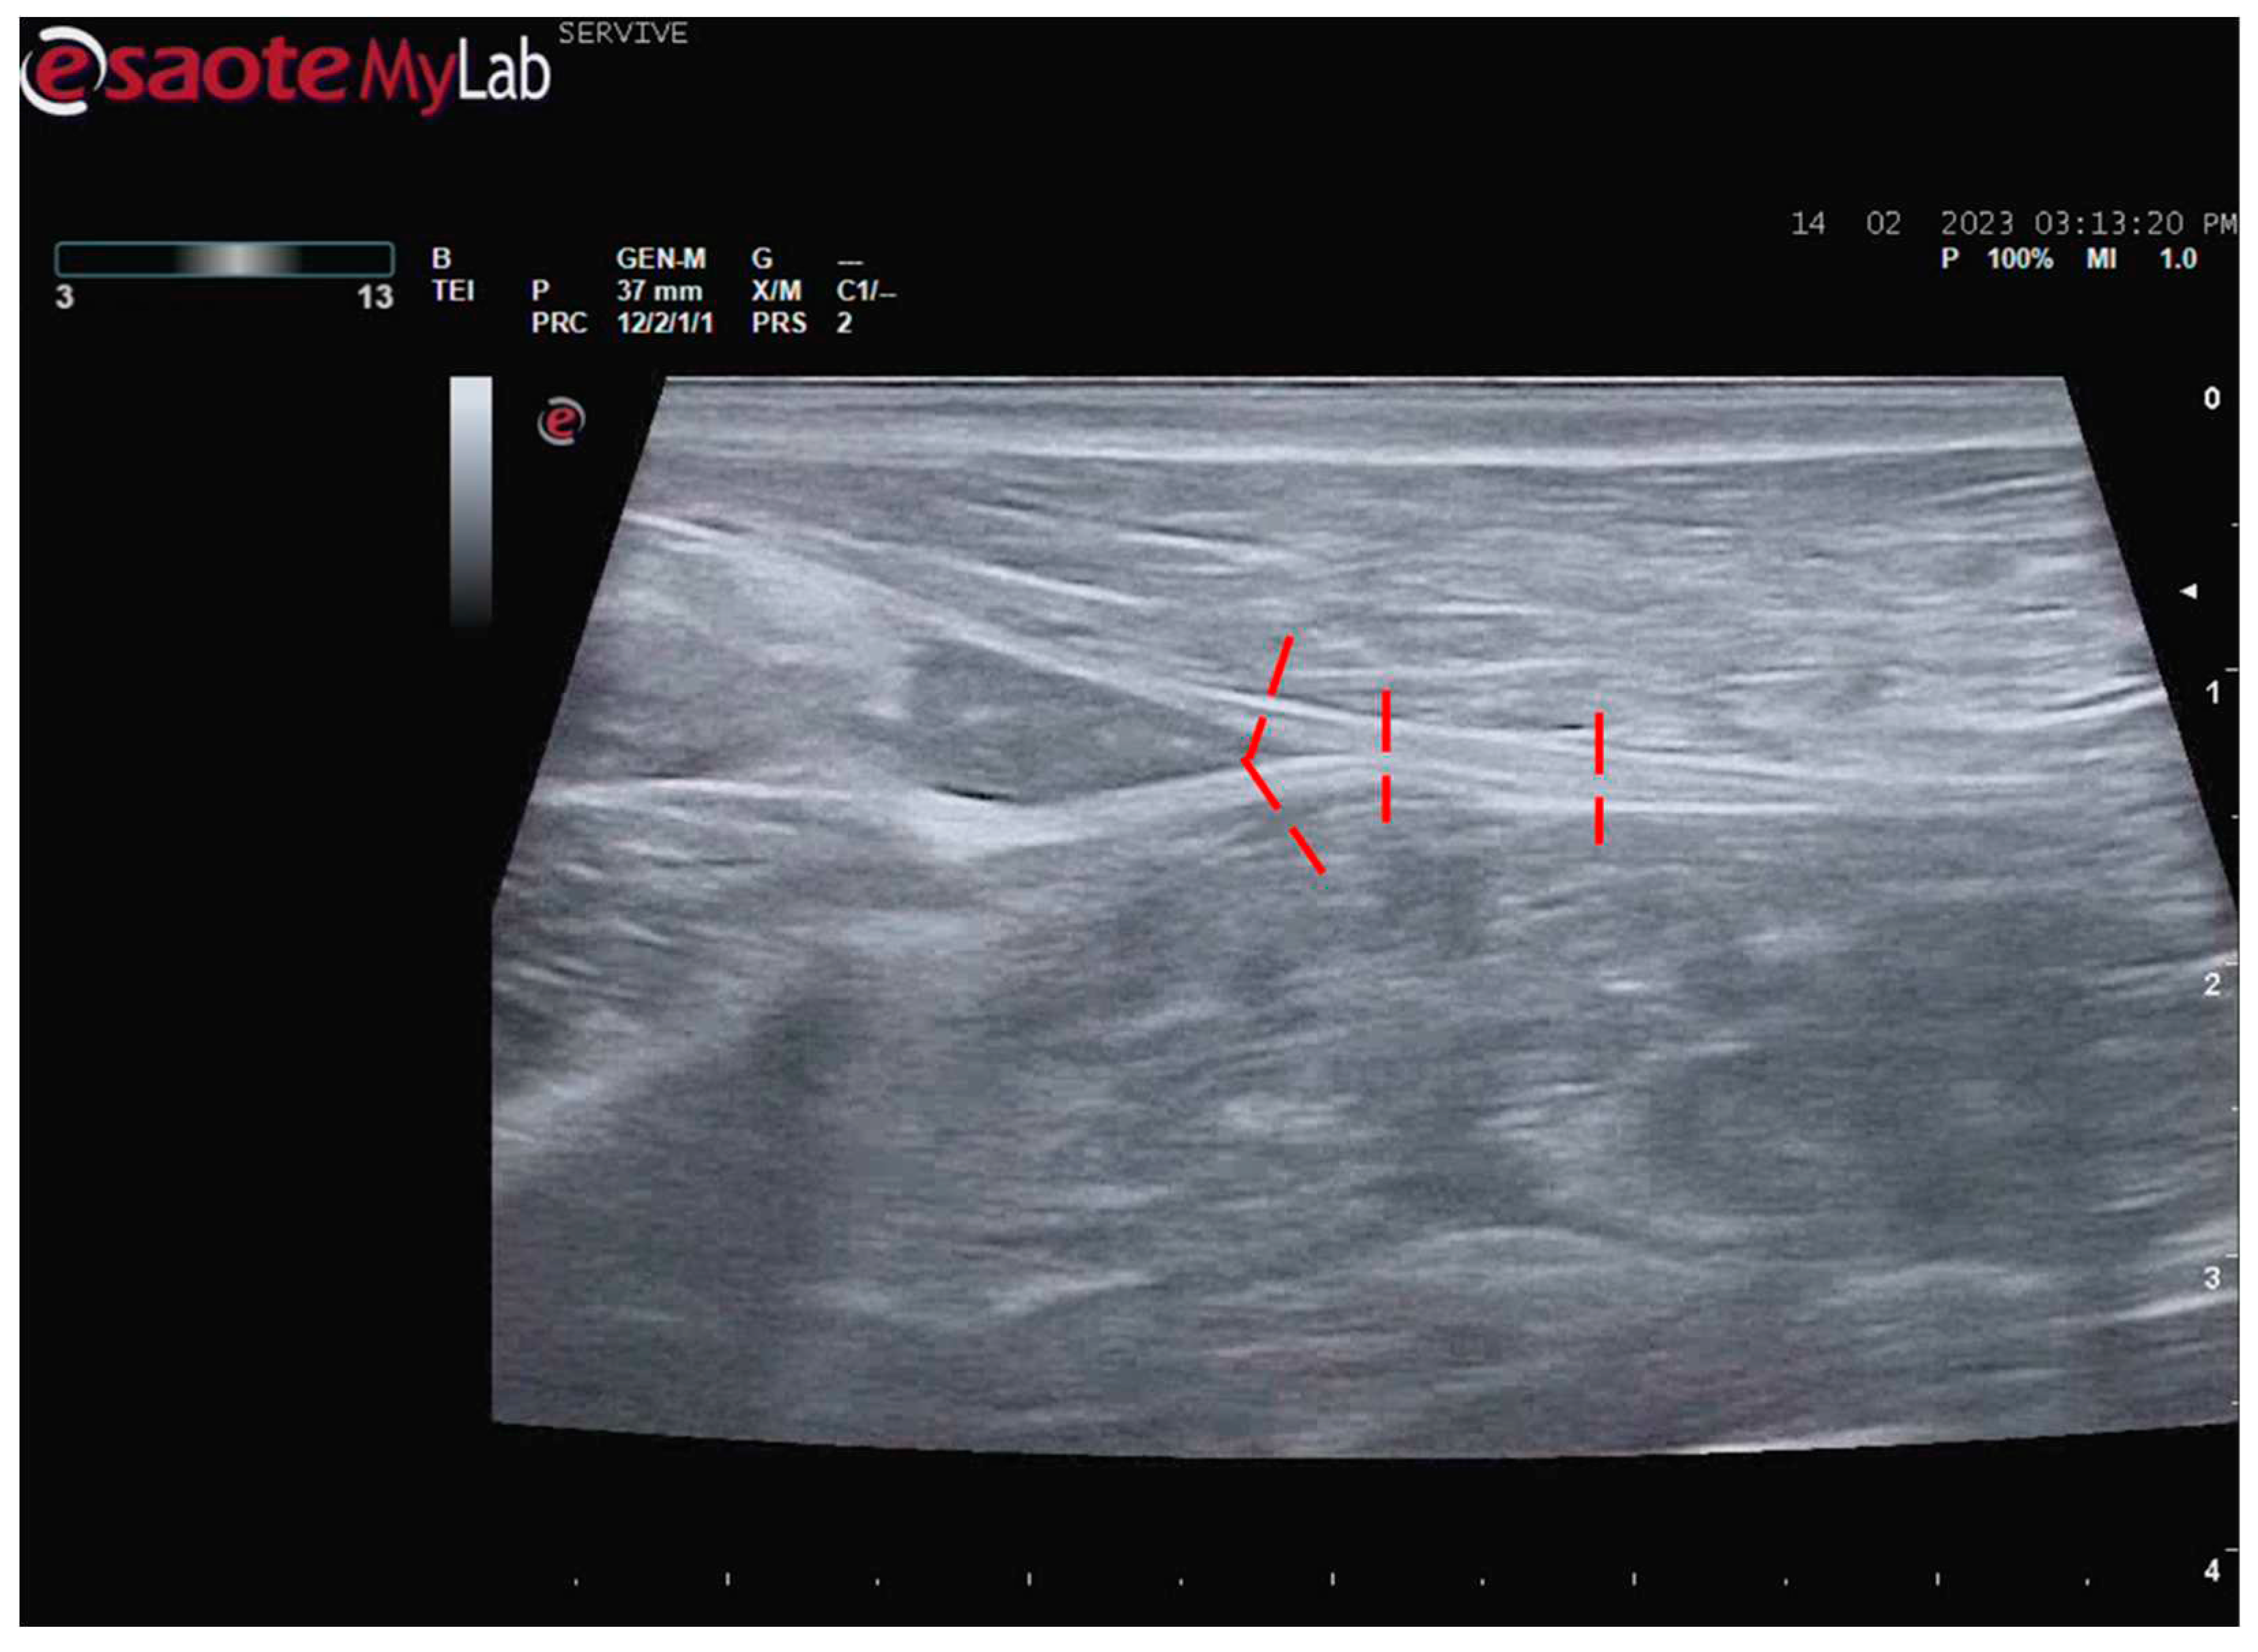

Figure 8.

Ultrasound image of the left sciatic nerve before its branching site, cross section (black arrow). In this plane, the nerve appears as an echogenic tubular structure surrounded by the musculature of the region. 1) biceps femoris muscle; 2) vastus lateralis muscle; 3) adductor muscles. DIST1 represents the measurement of the diameter of the sciatic nerve before its branching site.